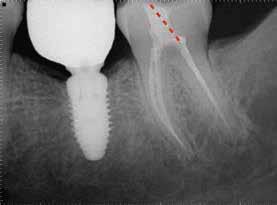

Egy 38 éves nőbeteg a korábban kezelt jobb felső második kisőrlőfogából (1.5) kiinduló mérsékelt fájdalom miatt jelentkezett rendelésünkön. A kórtörténetében jelen panasza szempontjából releváns információ nem szerepelt. A beteg a klinikai vizsgálat során vertikális kopogtatásra enyhe érzékenységet jelzett. A kérdéses fog körül mérhető szondázási mélység és a fogmobilitás fiziológiás volt. Periapicalis röntgenfelvételen egy, a fog gyökércsúcsán túl presszálódott betört gyökérkezelő műszerből származó eszközfragmentumot láttunk (2. a. ábra). A preoperatív CBCT-felvétel a buccalis csontlemez épségét igazolta (2. b-c. ábra). A fog revíziója öt hónappal korábban történt. A már előzőleg gyökérkezelt, gyökértömött, majd revideált 1.5-ös fog esetében a diagnózisunk periodontitis periapicalis symptomatica volt. A periapikális elváltozás kezelése érdekében navigált endodonciai mikrosebészeti beavatkozást végeztünk.

A felső állcsontról intraorális szkent (TRIOS) készítettünk, és az ezáltal kapott STL fájlt (2. d. ábra) a CBCT-felvétel során nyert DICOM fájlokkal a Zirkonzahn.Implant-Planner (Zirkonzahn) szoftverben egyesítettük. A sebészi sablont ebben a programban megterveztük, majd a Meshmixer (Autodesk) szoftver se-

a-m. ábrák: Preoperatív röntgenfelvétel (a) és preoperatív CBCT-felvétel a jobb felső 5-ös (1.5) fogról, sagittalis (b) és axialis (c) nézetek. Az intraorális szkennelés során kapott STL-fájl (d). A 1.5-ös fog navigált endodonciai mikrosebészeti beavatkozásához tervezett sablon (e). A 1.5-ös fog navigált endodonciai mikrosebészeti beavatkozásához nyomtatott sablon (f). Teljes vastagságú mucoperiostealis lebenyt emeltünk (g). A sablont a helyére illesztettük, és a csontablak határait jelöltük (h). A fog gyökerén kívül eső, betört eszköz a 1.5-ös fog periapicalis régiójában (i). Az eltávolított betört eszköz (j). A rezekció, retrográd preparáció és a TotalFill BC RRM Fast Set Putty anyaggal elkészített retrográd gyökértömés utáni röntgenfelvétel (k). A lebenyt varratokkal rögzítettük (l). A kétéves kontroll során készített röntgenfelvétel (m).

gítségével tovább módosítottuk. Az így kapott sebészi sablon egyértelműen meghatározta a periapikális terület eléréséhez szükséges csontablak határait (2. e-f. ábra) Helyi érzéstelenítést követően teljes vastagságú mucoperiostealis lebenyt képeztünk, majd a buccalis csont feltárását követően (2. g. ábra) a sablon segítségével bejelöltük a preparálandó csontablak határait (2. h. ábra). A csontablak kialakítása során Piezotome CUBE LED kézi-darabot alkalmaztunk, majd a leemelését követően a betört eszközt megkerestük (2. i. ábra) és eltávolítottuk (2. j. ábra). A rezekciót ultrahangos megmunkáló fejekkel (ACTEON) végeztük, majd retrográd preparáció következett.

A retrográd gyökértömés elkészítése során TotalFill BC RRM Fast Set Putty-t (FKG) használtunk (2. k. ábra). A lebeny széleit 5/0-s Prolene varratokkal egyesítettük (2. l. ábra). A varratok a műtétet követően 72 órával kerültek eltávolításra. A beteg két évvel később kontrollröntgen készítése céljából érkezett rendelőnkbe. A vizsgálat során a fog tünetmentesnek és funkcióképesnek bizonyult (2. m. ábra).